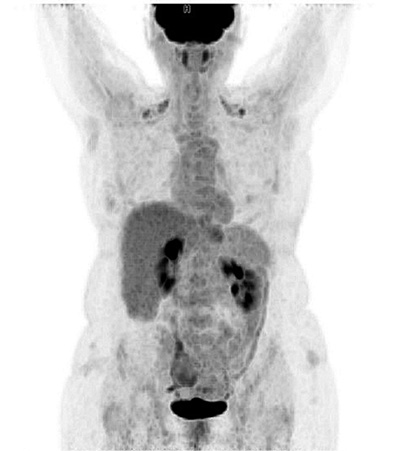

Contrast-enhanced Computerized Tomography (CECT) of the abdomen was the next diagnostics tool. The small intestine was presented with dilated loops, formed “air fluid levels” and free fluid in the Douglas pouch. The tumor formation itself was not detected by the radiologist on this scan (Figure 2).

Figure 2. CECT of abdomen with signs of small bowel obstruction